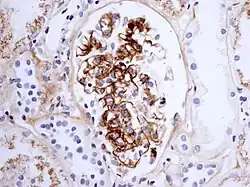

Immunostaining showing IgA in the glomerulus of a patient with Henoch-Schönlein nephritis.

The disease derives its name from deposits of immunoglobulin A (IgA) in a granular pattern in the mesangium (by immunofluorescence), a region of the renal glomerulus. The mesangium by light microscopy may be hypercellular and show increased deposition of extracellular matrix proteins. In terms of the renal manifestation of Henoch–Schönlein purpura, it has been found that although it shares the same histological spectrum as IgA nephropathy, a greater frequency of severe lesions such as glomerular necrosis and crescents was observed. Correspondingly, HSP nephritis has a higher frequency of glomerular staining for fibrin compared with IgAN, but with an otherwise similar immunofluorescence profile.[4]